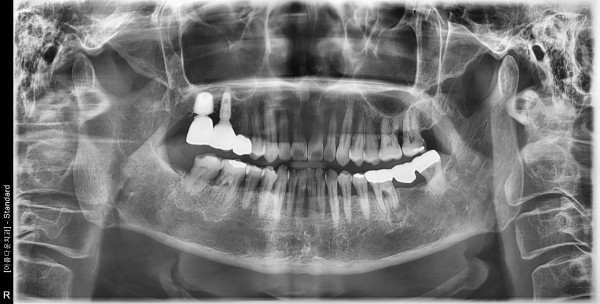

57세 여자 하악 좌측 구치부, 상악 우측 구치부 뼈 이식후 임플란트 식립